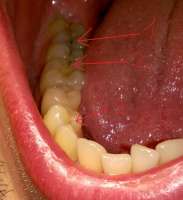

14734355806570.jpg (1325Кб, 1404x1076)

Антуаны, снова нид хелп. Я все тот же Антоний >>512791

Заделал все верхние зубы, в четверг иду ставить брекеты на "верх". Снизу остался 1 зуб с кариесом, его я удалю и вот эта вот хуйня, что я пытался нарисовать на пике выше. Под зубом 46 живет-растет НЕХ. Я оставил КТ терапевту или как там его, он посмотрел и сказал, что видимо когда то залечили мне тот зуб хуевасто, что-то осталось и вот эта хуйня развилась и по-тихоньку хуует там внутри меня. Сказала, что гарантий никаких на лечение дать не может: мб каналы не "пройдет", мб ухудшится ситуация, мб лечение не поможет и придеться удалять - очень шаткая ситуевина. В чем мой вопрос, казалось бы? А вопрос в том: что блядь делать то мне с этой хуйней? Она где то там внутри, жить не мешает, не чувствуется, не видится(ну кроме как на снимке), зуб я тот делал уже и не помню сколько лет назад. МБ 10-12. Но и она и ортодонт говорят одно и тоже: это бомба замедленного действия, может выскочить в любой момент и будет пиздец. Вроде терапевт сказала, что кость там задета этой хуергой или костная ткань. Что-то типа того.

Варианты следующие:

1. Пока есть месяц-полтора до постановки на нижнюю челюсть заняться зубов, просверлить его, положить "лекарство", временную пломбу заделать, надеяться, что пронесет и ставить брекеты. Но есть шансы, что все накроется пиздой, зуб в итоге хуй сохранишь, все мне там распидорасят и будет у меня дыра. А как же тогда брекет лепить? Слепок то делался под все зубы.

2. Нихера не трогать, ставить брекеты, а заняться через полтора года, когда систему сниму. Надеяться, что пронесет. Деньги пустить на сами брекеты, а когда уже все зубы будут как надо, ровные и тд - заниматься этой хренью. Если тогда уж удалять, то думать там - мост/имплант или что.

3. Есть еще мутный третий вариант это ходить по клиникам с этим моим КТ и спрашивать, кто возьмется мне эту херню лечить и будет уверен в результате. Но чувствую, все будут говорить, что гарантий никаких, давай неси бабки и раскрывай рот.

Встанет это все не меньше 10 тысяч, а я так вангую, что 15 точно отвалить придется и хуй бы с ним, если бы результат был, а так можно 15 отдать и в итоге получить дыру.

Грамотный анон, что делать то мне? В четверг пойду к ортодонту, скажу ему, что сказал терапевт, надо будет решение принимать какое-то. В какую сторону мне смотреть?